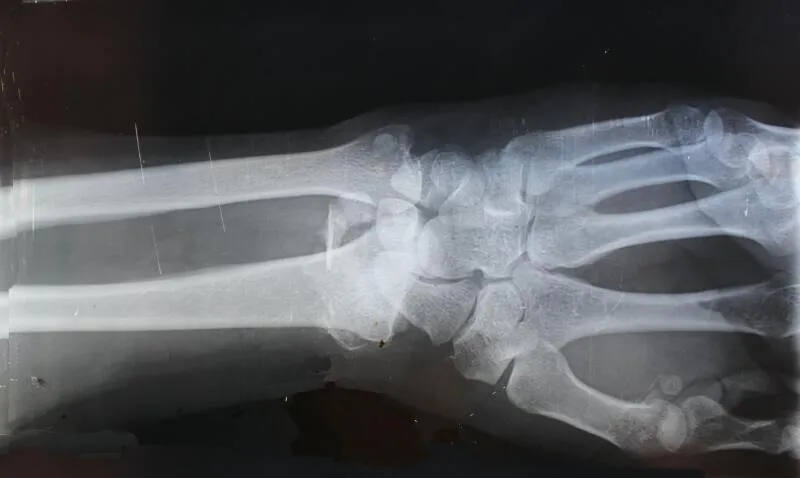

Zwykle opisywane są badania radiologiczne, które umożliwiają obrazowanie ciała człowieka. Do takich metod zalicza się przede wszystkim: tomografię komputerową (TK), rezonans magnetyczny (MR) oraz podstawowe badania obrazowe RTG (radiografia konwencjonalna).